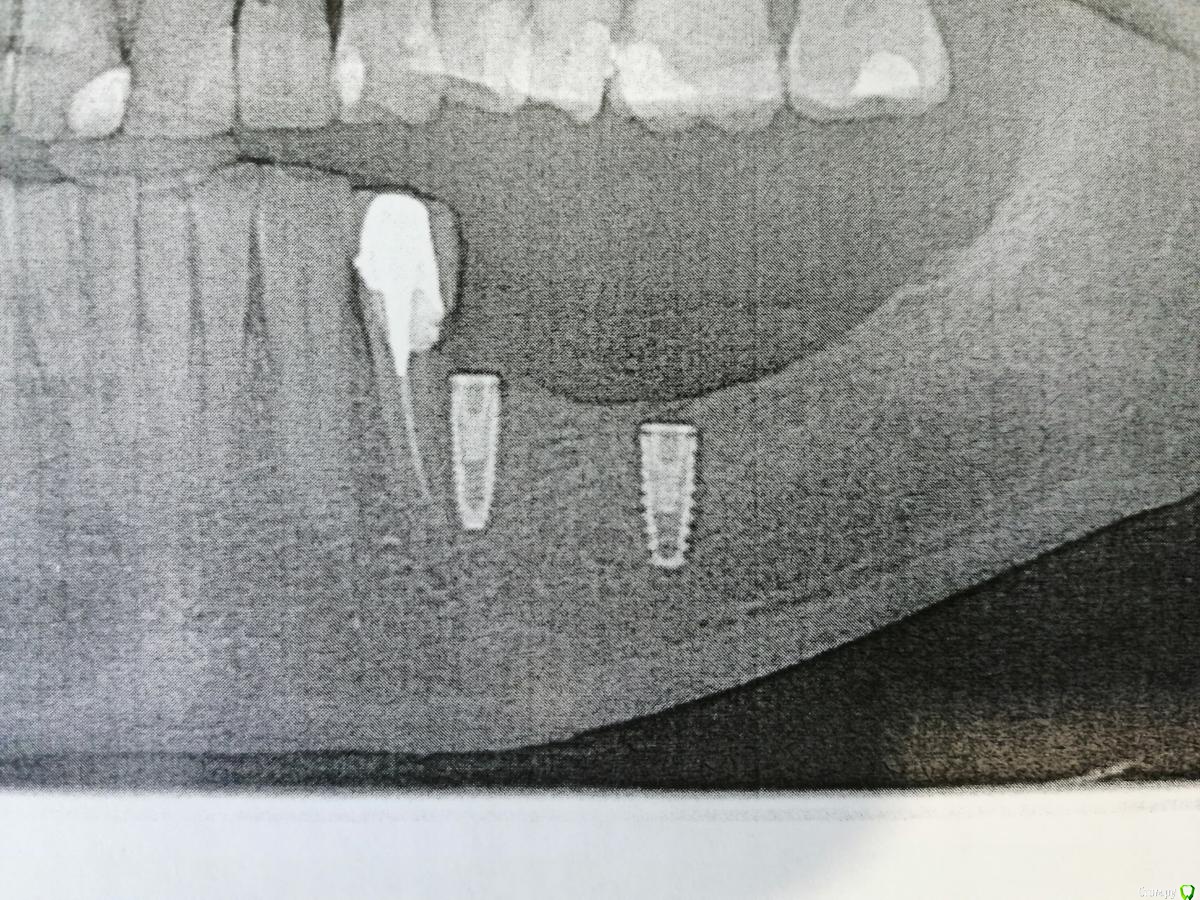

vadyasti Опубликовано 18 октября, 2018 Поделиться Опубликовано 18 октября, 2018 Добрый день коллеги! Подскажите пожалуйста ортопеду, какая это система имплантов? Ссылка на комментарий

Irouil Опубликовано 18 октября, 2018 Поделиться Опубликовано 18 октября, 2018 Похоже на Nobel replace Ссылка на комментарий

red_butler Опубликовано 18 октября, 2018 Поделиться Опубликовано 18 октября, 2018 Похоже на Nobel replaceНе похоже 2 Ссылка на комментарий

Nazim_NV86 Опубликовано 18 октября, 2018 Поделиться Опубликовано 18 октября, 2018 Полые до кончиков... Ссылка на комментарий